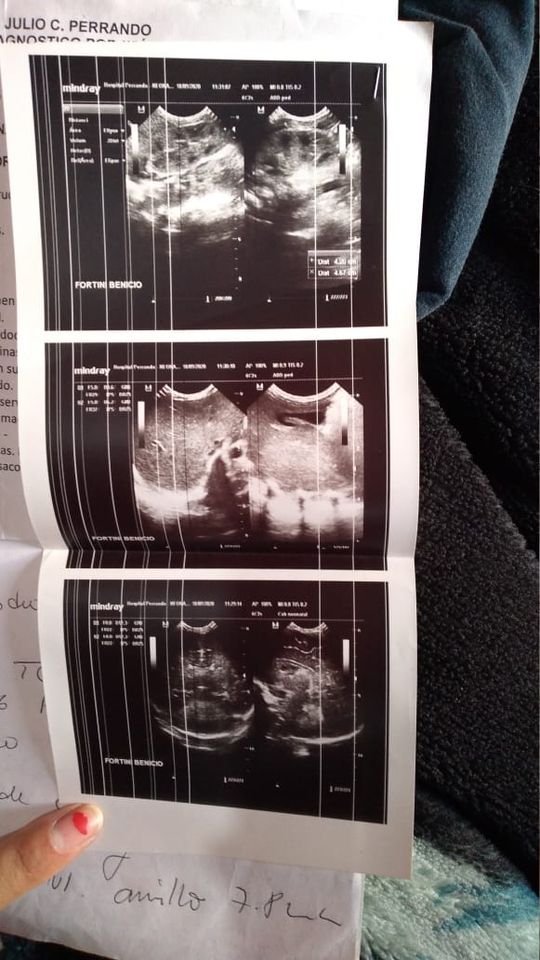

Benicio Escobar, de tan sólo un mes de vida, se encuentra en estado delicado de salud y tiene que viajar Buenos Aires, donde recibirá un tratamiento en el hospital Posadas.

“Tiene tapadas las arterias del corazón. Entre el miércoles o jueves, a más tardar, lo llevan al Posadas, allí le pondrán sondas y si en 20 días no se abren las arterias, lo tendrán que operar”, contó la tía del bebé que el 18 de octubre cumplió su primer mes de vida.